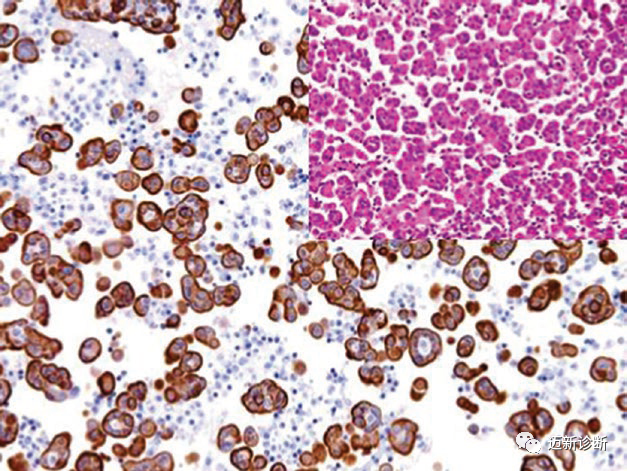

CK7表达于大部分导管上皮及腺上皮以及尿道的移行上皮。CK7是不同来源腺癌鉴别诊断的主要指标之一,因此不能单独用于原发和转移性腺癌的鉴别;CK7在间皮细胞为强阳性表达,因此不适用于腺癌和间皮瘤的鉴别。应用陷阱:腺癌与鳞癌鉴别诊断时,一定要牢记,某些部位的鳞状细胞癌中可有少量CK7阳性细胞,具体如头颈部、肺部、食管、宫颈,主要见于低分化癌。CK7也可表达于非上皮性肿瘤,如滑膜肉瘤中的上皮样成分。精原细胞瘤、卵黄囊瘤、前列腺癌、垂体肿瘤一般不表达CK7。CK20为中间丝蛋白,是成熟肠上皮细胞及胃肠道黏膜杯状细胞中的主要蛋白。结直肠腺癌、卵巢黏液癌中CK20总是阳性,移行细胞癌中阳性比例降低。Merkel细胞癌中,CK20呈核旁逗点状阳性。

图3. Merkel细胞癌中,CK20呈特征性的核旁逗点状着色。